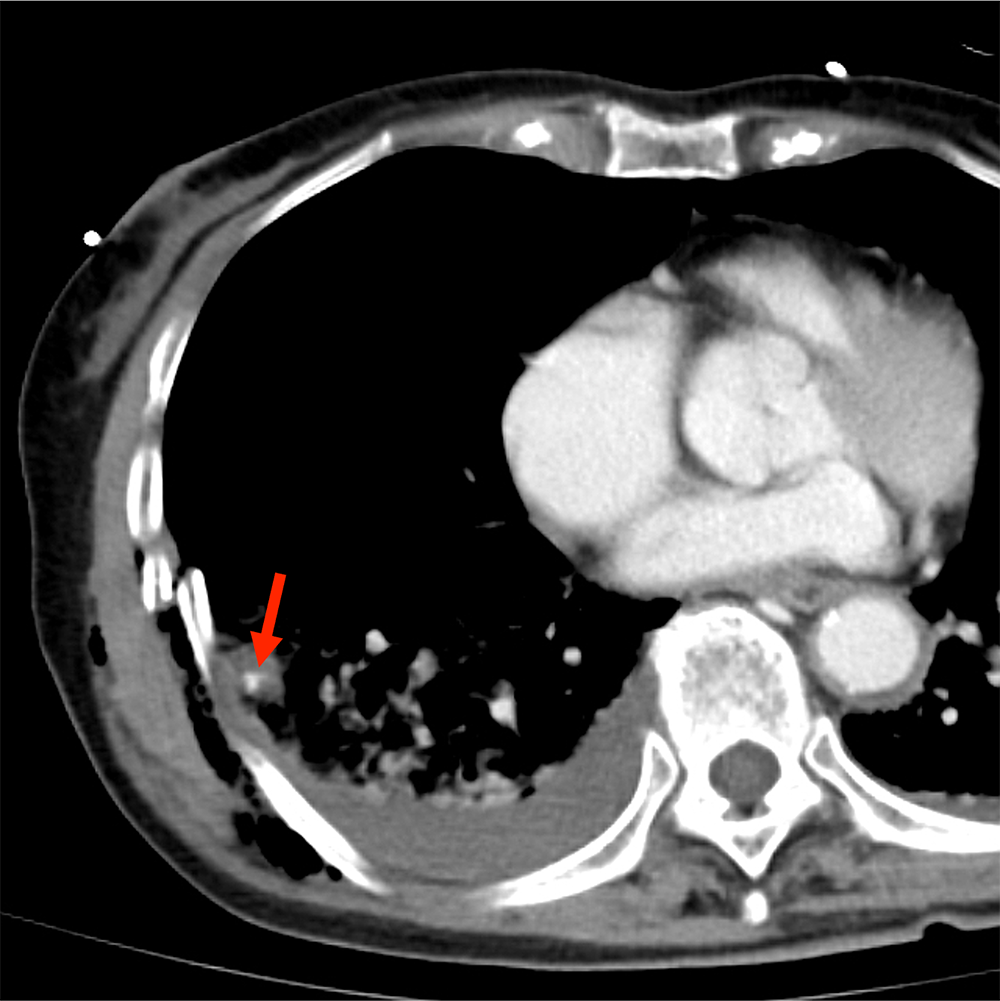

CTでは多発肋骨骨折、外傷性血気胸、肺挫傷、胸壁内気腫が認められた。

挫傷した肺内には結節状構造がみられ、肺気瘤の形成が示唆される。造影CTではこの内部に点状の濃染影が認められ、肺実質内血管外漏出(extravasation in the lung:EVIL)が疑われた。

肺挫傷や血気胸は単純CTでも確認できるが、造影CTを追加することで肺内血管外漏出(EVIL)の有無を確認することができる。

血管外漏出は活動性出血の存在を示唆する兆候で、外傷時のCTではまず確認すべき重要な所見である。腹部や骨盤部での血管外漏出は直ちに手術やIVRの適応になることが多いので、読影の際に見落としてはならない所見として認知されているが、肺挫傷で血管外漏出の有無を確認することの重要性はあまり知られていない。